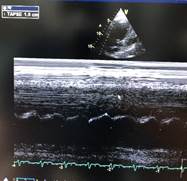

Bajo ese contexto sospechando TEP para confirmar el diagnóstico se realiza Angio-tc de vasos pulmonares (Fig.2 ), que mostro falta de captación de medio de contraste en arteria pulmonar derecha , en cuanto a los exámenes de laboratorio lo más relevante fue troponina 4,7630 u/l , dímero-d 54490,00 ng/ml , ferritina 27300,00 ng/ml. Se procedió a iniciar tratamiento fibrinolítico, que al no contar con r-tpa (alteplase) se usó estreptoquinasa 1.500.000 UI  que fueron administradas de forma intravenosa en una hora, seguida de anticoagulación con enoxaparina, después se evidencio mejoría en la oxigenación y hemodinámica, a las 24 horas se realiza nuevo rastreo ecocardiográfico (Fig. 3) en el cual existe mejoría de función ventricular derecha.

Figura 3. Ecocardiograma Post-fibrinólisis. A función sistólica de VD adecuada TAPSE 1,9. B Cavidades derechas normales.